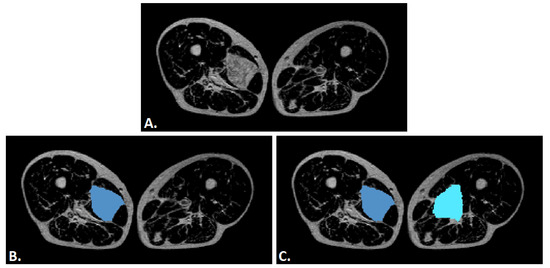

Although the dataset does not include scans from healthy subjects, regions of healthy tissue were extracted from the MRI scans of sarcoma patients, as illustrated in Figure 3. These regions were manually selected to represent non-pathological anatomy and were used to provide negative samples during model training. This method yielded 175 samples, contributing to a dataset balanced not only in terms of sample count. As a matter of fact, this approach ensures that both tumor and non-tumor tissue characteristics are learned within the same imaging context. The number of healthy tissue samples is moderately lower than that of sarcoma samples, as not all scans contained sufficient healthy tissue for safe segmentation. In such cases, the corresponding healthy images were excluded to prevent volumes from potentially containing tumor traces.

Figure 3A shows the original MRI image with a unilateral soft tissue sarcoma. Figure 3B displays the manual segmentation of the tumor region (blue) on the affected side, while Figure 3C illustrates the corresponding extraction of healthy tissue regions (light blue) from the contralateral limb. These were used as negative samples for training, in contrast to the tumor region (blue) used as the positive sample. This strategy enables intra-patient comparison under consistent imaging conditions.

Figure 3. Example of tumor and healthy tissue segmentation in axial T1-weighted MRI of the thighs. (A) shows the original MRI with a unilateral soft tissue sarcoma. (B) displays the manual segmentation of the tumor (blue), while (C) shows the corresponding healthy tissue regions (light blue) from the contralateral limb, used as negative samples.